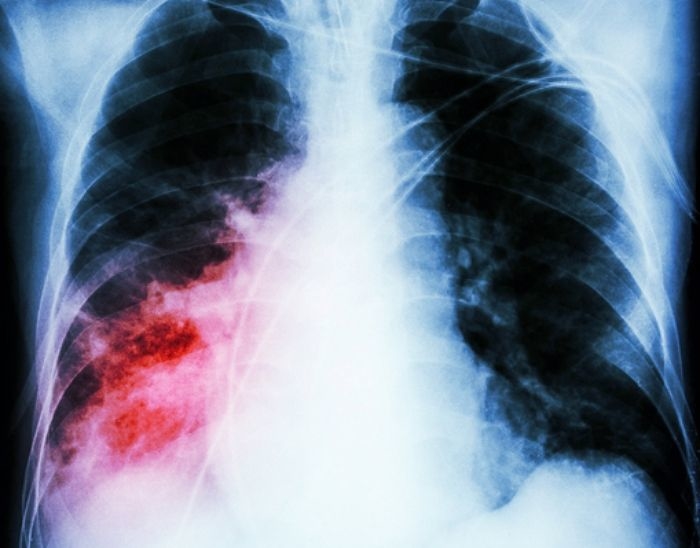

기사의 이해를 돕기 위한 자료 사진 / gettyimagesBank기사의 이해를 돕기 위한 자료 사진 / gettyimagesBank

img_20210308171750_m1k69380.jpg기사의 이해를 돕기 위한 자료 사진 / gettyimagesBank